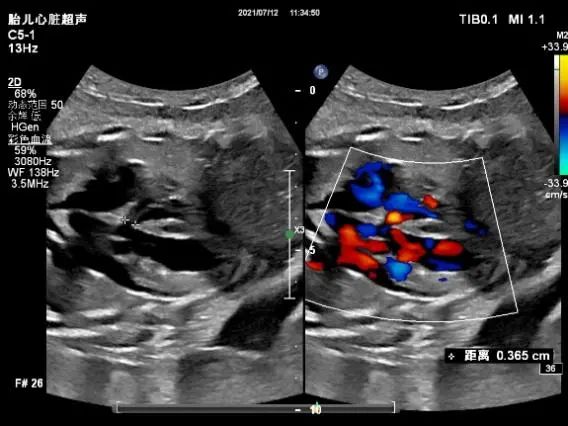

孕妇34岁,怀孕29周,在当地医院产检提示:大血管连接异常。随转至武汉大学中南医院就诊,产前超声显示:内脏、心房正位,左位心,心室右袢,房室连接一致,心室与大动脉连接不一致,完全性大动脉转位(S.D.D),小室间隔缺损可能(见下图)。

左室(LV)与肺动脉(PA)连接,右室(RV)与主动脉(AO)连接。室间隔似见一内径约0.3cm缺损(白色箭头所示)。